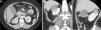

TCMC, en planos (a) axial (b) coronal y (c) sagital, de una mujer de 49 años con carcinoma de células claras de 5,5cm (flechas). La línea blanca delimita dónde debería estar el contorno renal para determinar el componente E (exofítico/endofítico). La masa se encuentra más del 50% exofítica, por lo que E es igual a un punto. Se pueden utilizar cualquiera de los planos. RS: 2+1+1+a+1=5a (baja complejidad quirúrgica).

TCMC, en planos (a) axial, (b) coronal, (c) axial en fase excretora y (d) sagital, de una mujer de 48 años de edad con carcinoma de células claras de 2cm (flechas). El tumor se encuentra menos del 50% exofítico, en relación con la línea blanca que delimita el contorno renal, por lo que E es igual a dos. RS: 1+2+3+x+3=9x (mediana complejidad quirúrgica).

TCMC, en planos (a) axial, (b) coronal, (c) axial en fase excretora y (d) sagital, de una mujer de 26 años de edad con carcinoma de células claras de 3cm con bordes calcificados (flechas). La masa es completamente endofítica, por lo que E es igual a tres. RS: 1+3+3+x+2=9x (mediana complejidad quirúrgica).